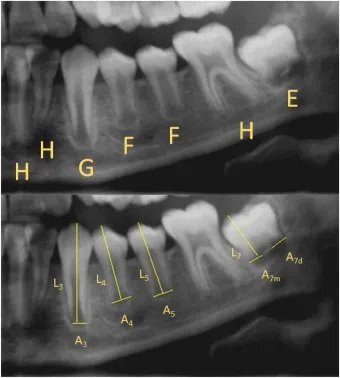

- Assesses 8 mineralization stages (A-H) for 7 left mandibular teeth.

- Scores summed, converted to dental age using specific population tables.

⭐ While Demirjian's method (using 8 stages A-H for 7 left mandibular teeth) remains widely used, newer 3D imaging technologies and computational approaches are increasingly employed in forensic odontology for enhanced precision in age estimation under BSA evidence standards.